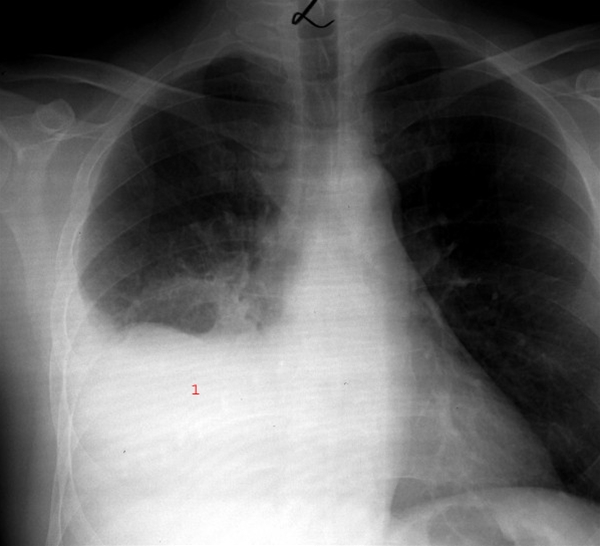

Røntgen af lunger med betændelse

Lægen spørger ind til din sygehistorie og undersøger dig, hvilket kan være tilstrækkeligt til en sikker diagnose.

Blodprøver, som høj CRP og et øget antal hvide blodlegemer, kan styrke lægens mistanke om lungebetændelse.

I enkelte tilfælde ønsker lægen, at der bliver taget et røntgenbillede af lungerne for at bekræfte eller afkræfte, om du har en lungebetændelse.